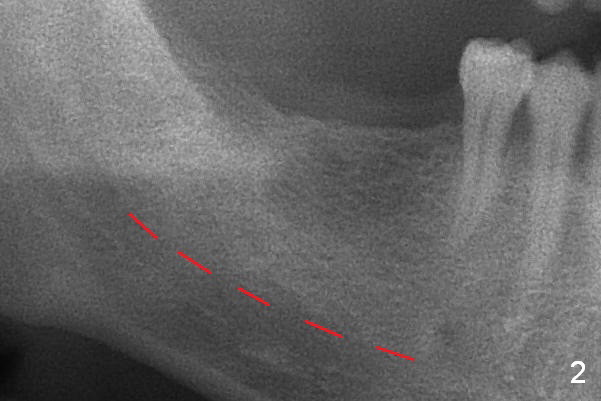

The bone height is good (Fig.2 (red dashed line: the superior border of the Inferior Alveolar Canal)). Implants at #30 and 31 are expected 5x12 or 14 and 5x10 or 12 mm, respectively. The abutments are 6.8x4(2) and 6.8x4(1) mm.